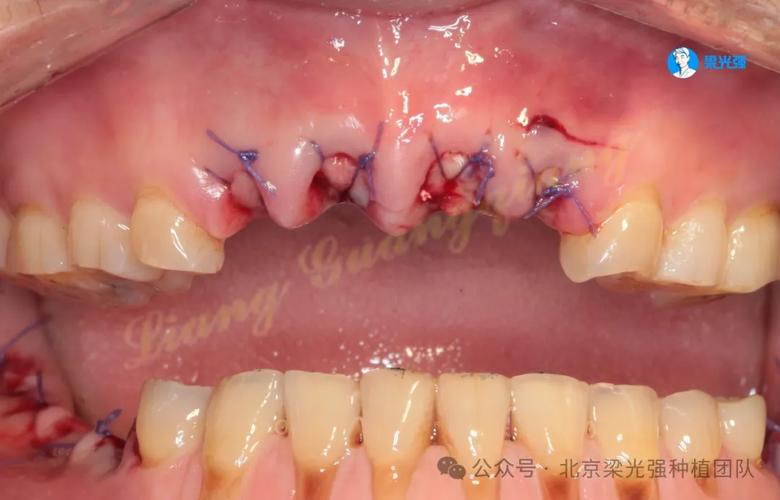

- 感染控制:若为种植体周围炎,需先进行清创(刮除感染组织)、冲洗,并全身或局部使用抗生素;若感染严重,需取出种植体,待炎症完全控制(通常2-4周)后再评估。

- 取出种植体:对于松动明显、骨吸收严重的种植体,需及时取出,避免残留种植体碎屑影响骨愈合,取出后彻底清理种植窝,去除炎性肉芽组织。

- 骨增量处理:若骨量不足导致失败,可在取出种植体同期或延期进行植骨术(如自体骨移植、骨粉填充),使用骨引导再生膜(GBR技术)引导骨再生,待3-6个月骨愈合充分后,再行二次种植。

- 延期种植:对于骨条件较差、感染严重或软组织愈合不佳的患者,建议等待6个月以上,待牙槽骨稳定、血供恢复后再尝试种植,避免再次失败。